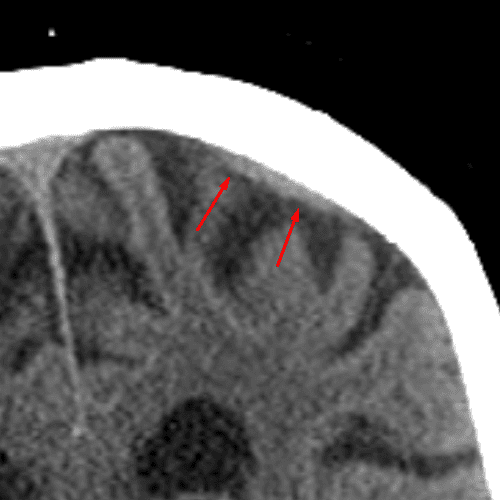

Mendosal Suture

Case 18